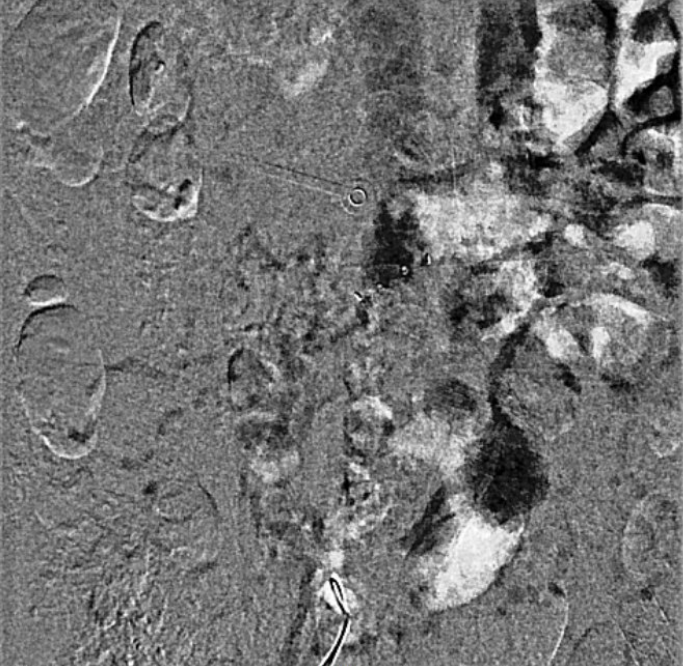

Venography showed occlusion of the right external and common iliac veins with collateral flow; popliteal and femoral veins were patent. A 6F sheath was placed in the right CFV, and a V-18 0.018 wire was advanced to the IVC. Attempts to traverse outside the prior left iliac-femoral stent for double-barrel reconstruction were unsuccessful, as the wire repeatedly entered the existing stent, likely due to complete apposition.The strategy was revised, and wiring into the IVC through a proximal stent strut was achieved. IVUS from the IVC to the RCFV confirmed severe compression at the right CIV ostium and proper wire position. A 10 ¡¿ 39 mm Abbott Omnilink balloon-expandable stent was deployed at the RCIV ostium and dilated to 10 atm. A kissing-balloon angioplasty was then performed with a 12 ¡¿ 40 mm Armada balloon from the LCIV and the RCIV balloon inflated simultaneously to 10 atm, restoring bifurcation geometry.A 14 ¡¿ 60 mm Bard Venovo stent was placed from the RCIV to the REIV and post-dilated with a 12 mm balloon to 10 atm. Final angiography showed widely patent, well-expanded stents with brisk antegrade flow into the IVC and no residual stenosis or thrombosis. Hemostasis was achieved with manual compression, and the procedure concluded without complications.

The patient achieved rapid clinical improvement with resolution of limb edema and remained free of recurrence under oral anticoagulation at follow-up.This experience highlights that in cases where conventional double-barrel iliocaval reconstruction is technically unachievable due to prior stent endothelialization or anatomic limitation, cross-strut recanalization combined with balloon-expandable stent implantation and kissing balloon angioplasty provides a feasible and durable alternative for iliocaval revascularization.